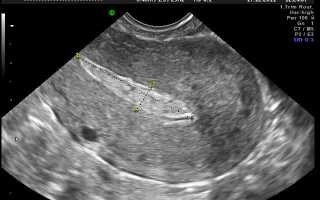

Матка после аборта на УЗИ

Основное, что видно на УЗИ в таком случае – это истонченный эндометрий. Но до определенного срока это является нормой. Можно на УЗИ также заметить и остатки продуктов гестации. То есть, иногда после аборта в полости матки остаются частицы плодного яйца, которые необходимо незамедлительно удалять, так как они могут стать причиной воспалительного процесса. Но остатки продуктов гестации обычно имеют место только при аборте на позднем сроке более 7 недель.

Гипоэхогенные включения на УЗИ могут быть признаком серьезных патологий. Они могут свидетельствовать о перфорации матки, говорить о скоплении в ней крови, остатках продуктов гестации, начинающемся эндометрите и т. д. Именно такой высокой информативностью УЗИ и объясняется то, что данная процедура почти всегда назначается после аборта.